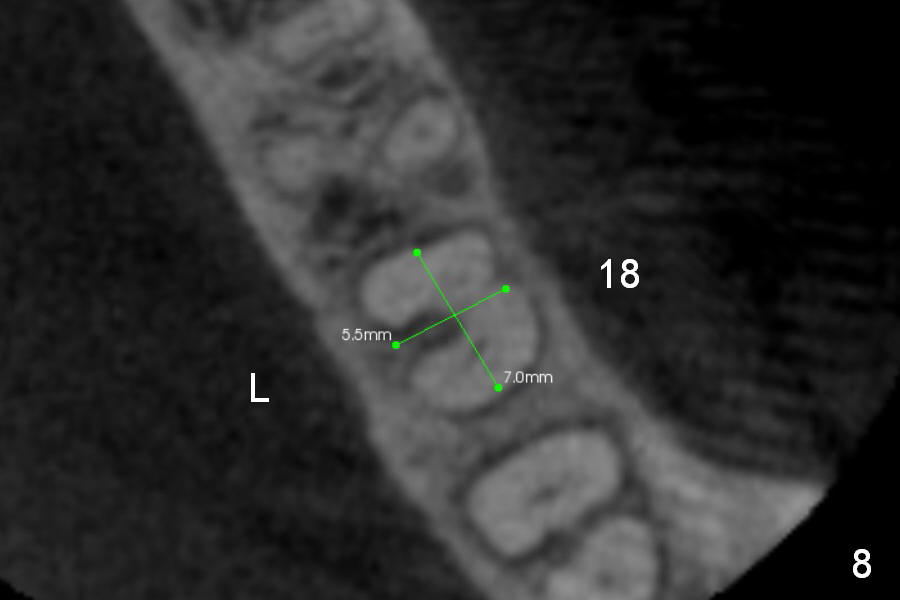

CBCT Analysis of the lower left 2nd molar reveals that the proper implant size is 5.3x10 mm (Fig.8-10). The root is C shaped; limiting factor is buccolingual width (5.5 mm, Fig.8 (axial section)). The major difference between #18 and 31 is the resorption of the buccal plate of the latter (traumatic extraction, Fig.9 (F: submandibular fossa)).